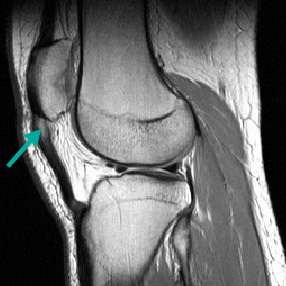

Best imaging modality for evaluating tendon injury.[34]

Allows for evaluation of surrounding soft tissues.

Normal tendons appear dark whereas degenerative tendons may appear thickened and will exhibit intermediate signal intensity (appears grey/white).[Figure caption and citation for the preceding image starts]: MRI demonstrating mild to moderate tendinopathy of the proximal centimetre of the patellar tendon, characterised by thickening and abnormal signal within the tendonFrom the personal collection of James Wang, PhD [Citation ends].

Result

thickened tendon with intermediate signal intensity (grey/white)